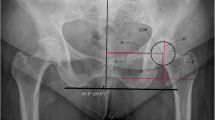

Lateral centre-edge angle (LCEA)

The LCEA (Fig. 4b) increased with age (r = 0.716; p < 0.0001). A strong significant correlation with gender or side was not found.

LCEA correlate significantly and strongly with CFHV (r = 0.792; p < 0.0001) and FHEI (r = − 0.683; p < 0.0001) as well as FHD (r = 0.643; p < 0.0001), AOS (r = 0.603; p < 0.0001) and POS (r = 0.645; p < 0.0001). Fast growth phases were noted at the age of 1 (15.72°–20.28°; 29%) and 7 (16.99°–23.18°; 36.43%) (Table 3).

A mean LCEA value of 24.1 ± 9.9° was measured in this study. The results are comparable with those of Novais et al. [22] where values of 26 ± 5° in the CT scans of asymptomatic adolescents aged 10–17 years were measured but lower than the values presented by Tönnis et al. [29], where a mean angle of 31.3 ± 2.36° was measured.

Tönnis et al. [29] further categorized his X-ray-based reference values and considered LCEA values of > 20° for children aged 5–8 years and > 25° for children aged ≥ 9 years to be a sign of sufficient femoral head coverage. In this study LCEA values of 19.4 ± 2.7° were measured in children 5–8 years old and 31.1 ± 11.5° in children ≥ 9 years old. The first values would have been considered marginally pathological according to the reference values of Tönnis et al. [29]. This suggests that the X-ray-based techniques may overestimate the actual values of these measurements.